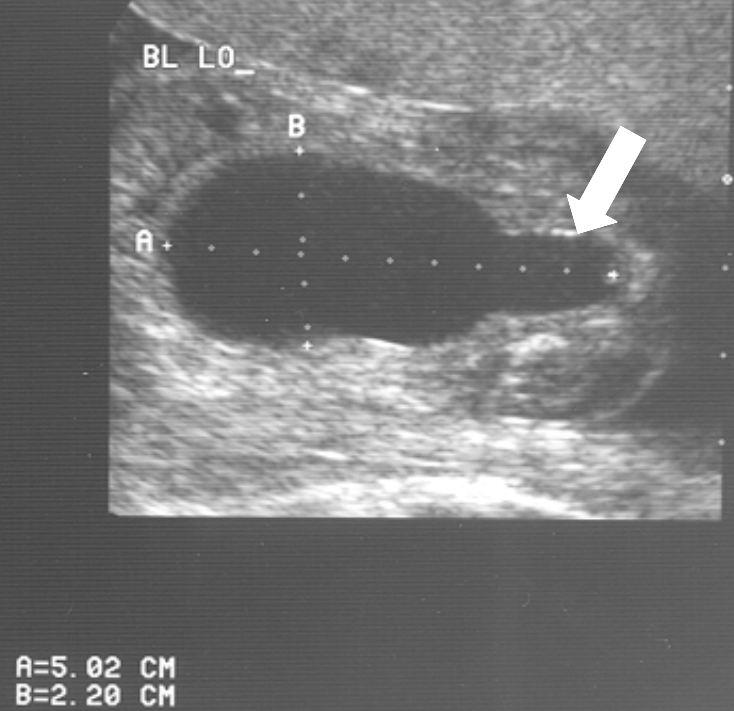

20 weken echografie: links: dikwandige blaas met verwijding van de plasbuis tot aan de kleppen (pijl): het “sleutelgat teken”. Onder: verwijde urineleiders. Bij kinderen gaan de urineleiders bij verwijding ook erg gekronkeld verlopen.

Verwijde nierbekkens (lange pijl) en nierkelkjes (korte pijl). Smalle nierschors.